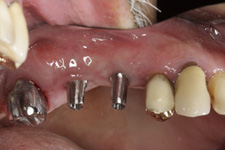

Protetické řešení může být pomocí můstku, který je kotvený na implantátech nebo pomocí jednotlivých korunek na implantátech.

V zásadě je možné do těchto můstků zařadit i přirozené zuby, zejména pokud je potřeba tyto zuby ošetřit proteticky – korunkami. Korunky nebo můstky mohou být na implantáty nacementovány nebo přišroubovány.

Zdravé zuby zůstanou zachovány a přitom náhrady jsou pevné, jako na vlastních zubech